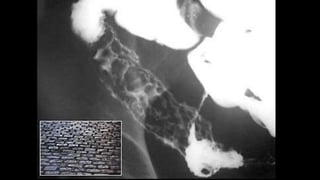

SIGNO DEL EMPEDRADO

• Signo de enfermedad de Crohn en el estudio baritado.

• La presencia de úlceras longitudinales y transversales,

con islotes de mucosa sana entre ellas, provoca la

apariencia de empedrado en la mucosa del segmento

intestinal afectado.

• Visible en intestino delgado y puede verse también en

el colon.

SIGNO DEL EMPEDRADO •Signo de enfermedad de Crohn en el estudio baritado. • La presencia de úlceras longitudinales y transversales, con islotes de mucosa sana entre ellas, provoca la apariencia de empedrado en la mucosa del segmento intestinal afectado. • Visible en intestino delgado y puede verse también en el colon.